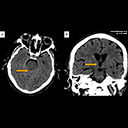

Computed tomography (CT) of the head (Figure 1A and B) and chest demonstrated obstructive hydrocephalus with tectum and midbrain edema and a 1.1 cm, noncalcified pulmonary nodule in the left lower lobe posteriorly (Figure 2).

- Figure 1A and B: Computed tomography of the head without contrast demonstrating obstructive hydrocephalus with tectum and midbrain edema